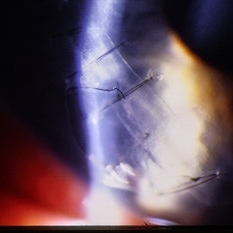

Surgical view- exposing globe to repair traumatic rupture.

Condition/keywords: trauma